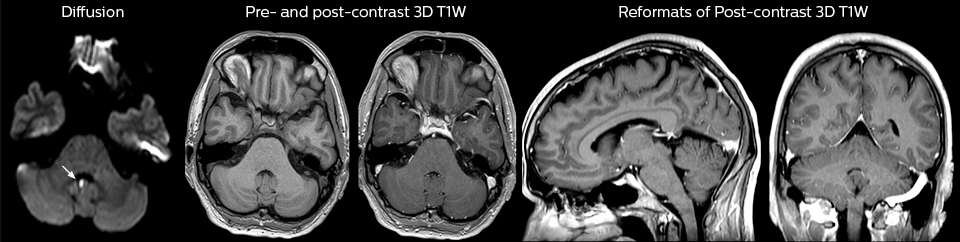

Pour minimiser la durée des acquisitions, des protocoles d’examen IRM rapides (ExamCards) ont été mis au point. Ils réduisent la durée d’acquisition totale à moins de 10 minutes pour certains examens. Des techniques comme le mDIXON (DIXON modifié) sont utilisées pour une acquisition solide des images d’IRM sans graisse dans l’environnement stressant des urgences.

Une gamme de feuilles de protocole a été développée. Objectif : s’assurer que les médecins traitants choisissent l’examen IRM le mieux adapté. Les protocoles d’IRM optimisés comprennent également une imagerie de contraste 3D permettant aux neurochirurgiens d’utiliser confortablement les données isotropes au bloc opératoire tout en réalisant la chirurgie stéréotaxique.